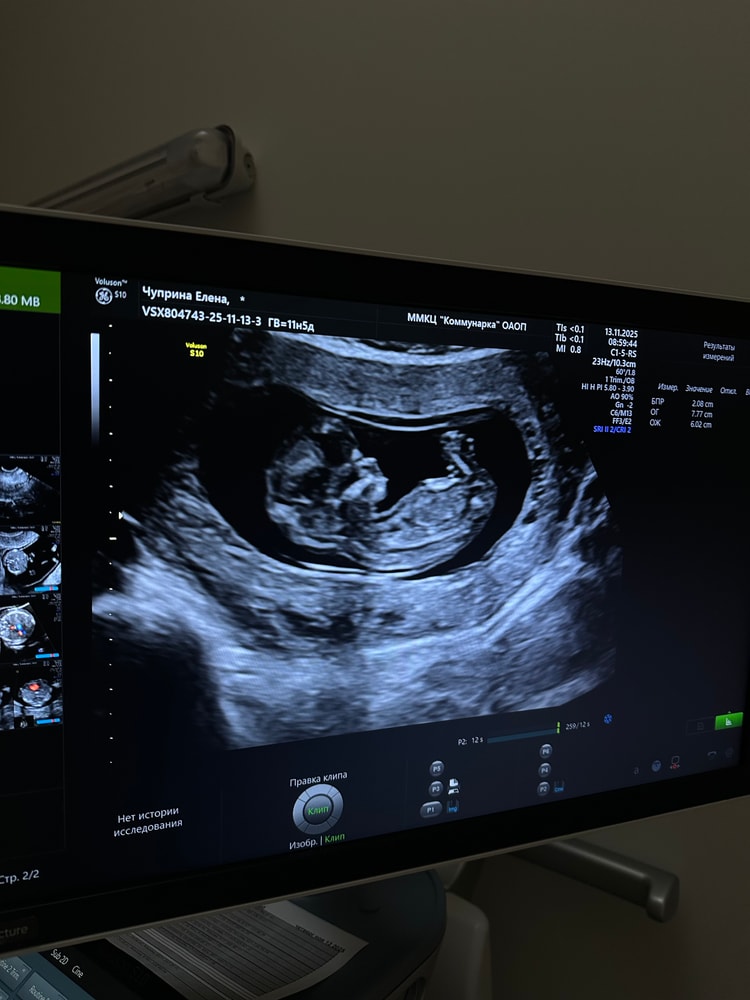

12 недель: 1 скрининг, УЗИ

Результаты УЗИВолнение и первые слова врача: «Плод есть, сердцебиение есть». Выдыхаешь сразу😅 Последний раз была на УЗИ 5 недель назад, когда малыш совсем крошечный был. А сегодня прям человек! Эти ножки, махающая ручка, личико🥹на меня похожа кроха (внизу фото)😁

Все хорошо: анатомия, органы🙏🏻 Скользил кроха так смешно, отталкиваясь ножками🥹

Развитие чуть опережает (где-то 12н6д, в чем-то 13н2дн, в итоге по УЗИ ставят в совокупности - 12н2д (по переносу 12 ровно, по мес. 11н5д).

КТР - 59 мм

ТВП - 1.6 мм

Носовая кость - визуализируется. С дочкой помню не визуализировалась на 1 скрининге и помотали мне нервы.

ЧСС - 163 уд/мин🫶🏼

В пуповине 3 сосуда. Плацента идеально расположена - по задней стенке. Для кесаренных это просто шикарно! Но низко. Надеюсь, с ростом малыша, поднимется🙏🏻Шов (рубец) в норме. Шейка матки - 39 мм.